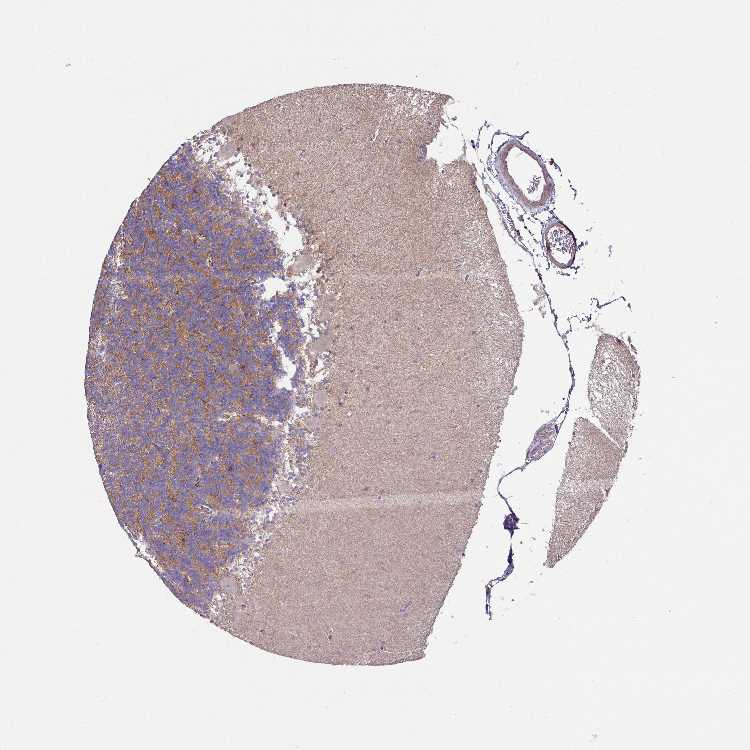

CEREBELLUM - Antibody stainingi

Antibody staining in the annotated cell types in the current human tissue is reported as not detected, low, medium, or high, based on conventional immunohistochemistry profiling in selected tissues. This score is based on the combination of the staining intensity and fraction of stained cells.

Each image is clickable and will lead to virtual microscopy that enables deeper exploration of all samples and also displays staining intensity scores, fraction scores and subcellular localization as well as patient and tissue information for each sample.

Antibody HPA051578

Bergmann glia - cytoplasm/membrane Not detected

Bergmann glia - nucleus Not detected

GLUC cells - cytoplasm/membrane Not detected

GLUC cells - nucleus Not detected

Purkinje cells - cytoplasm/membrane Not detected

Purkinje cells - dendrites Not detected

Purkinje cells - nucleus Not detected

Granular cells - cytoplasm/membrane Not detected

Granular cells - nucleus Not detected

Molecular layer - neuropil Not detected

Molecular layer cells - cytoplasm/membrane Not detected

Molecular layer cells - nucleus Not detected

Processes in granular layer Not detected

Processes in molecular layer Not detected

Processes in white matter Not detected

Synaptic glomeruli - capsule Not detected

Synaptic glomeruli - core Medium

White matter cells - cytoplasm/membrane Medium

White matter cells - nucleus Not detected